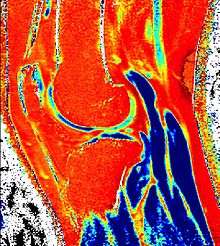

dGEMRIC T1 Map of knee cartilage

dGEMRIC T1 Map miliseconds